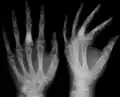

X-ray showing calcified enchondromas localized in finger a 37-year-old patient affected with Ollier disease

X-ray showing enchondromas localized in the lower part of the radius of a 37-year-old patient affected with Ollier disease